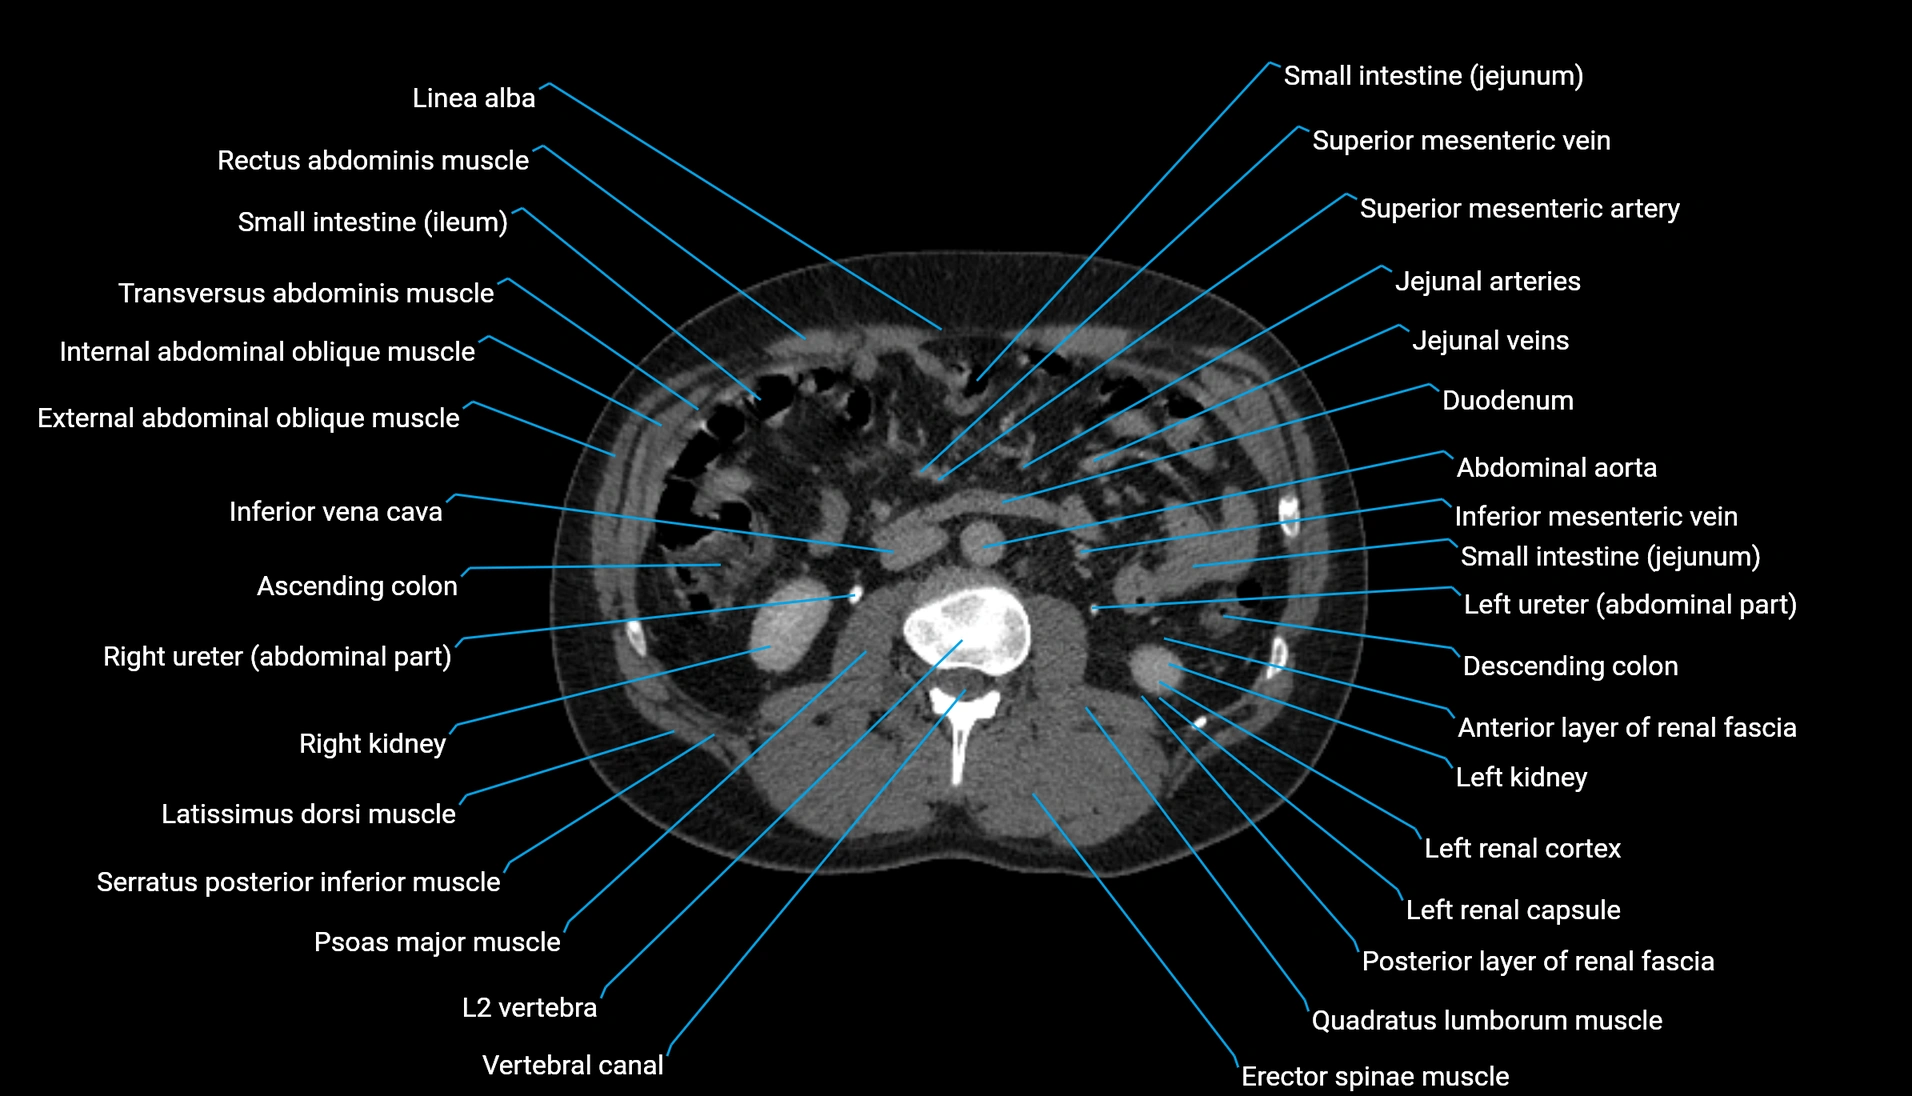

CT Appearance

Non-contrast CT:

-

Demonstrates cortical bone of acetabular rim in excellent detail

Detects fractures, dysplasia, retroversion, or bony overcoverage (pincer impingement)

3D reconstructions used in preoperative hip surgery planning

CT VRT 3D image

CT image